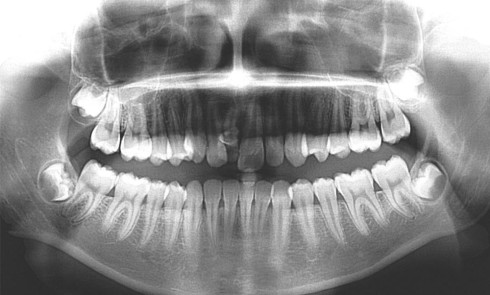

Grand Prix l’orthodontiste – Orthoplus Premier lauréat ex aequo Catégorie adultes Guillaume Lecocq Spécialiste qualifié en orthopédie dento-faciale, Valenciennes Diagnostic...